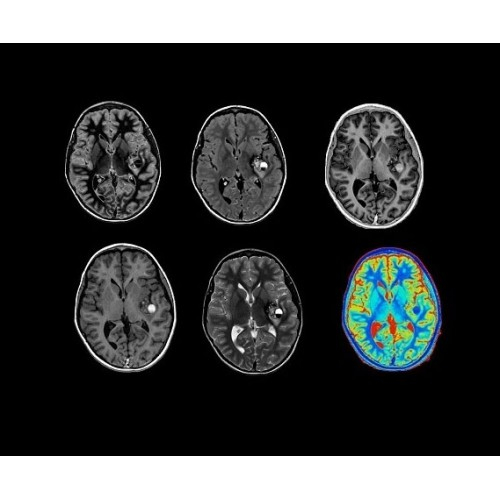

Компания GE Healthcare представляет революционную, полностью интегрированную систему SIGNA PET/MR1, в которой сочетаются времяпролетная технология (TOF) и возможности напряженности магнитного поля 3.0 Тл. Мы поможем вам поднять исследования на более высокий уровень. SIGNA PET/MR позволяет достичь впечатляющей точности и скорости исследований, а благодаря новейшей технологии реконструкции Q.Clear2 качество изображений улучшается в два раза. Кроме того, в систему включен полный набор клинических приложений и гибких катушек для проведения любых видов исследования, открывая для вас возможности визуализации, о которых вы даже не догадывались.

• Q.Clear — в основу технологии легли накопленные знания о том, как минимизировать помехи при реконструкции и получить четкое изображение. При значительном улучшении качества изображения сохраняется точность расчетов. Сочетание технологии TOF и реконструкции Q.Clear — ваш надежный помощник для получения точных и достоверных данных.

• Специальный пакет приложений для измерения и сравнения объемных изображений ЦНС с нормами поможет вам в диагностике нейродегенеративных заболеваний, а дополнительные инструменты визуализации — в постановке точного диагноза с помощью бета-амилоидов и радиоизотопных маркеров ФДГ.